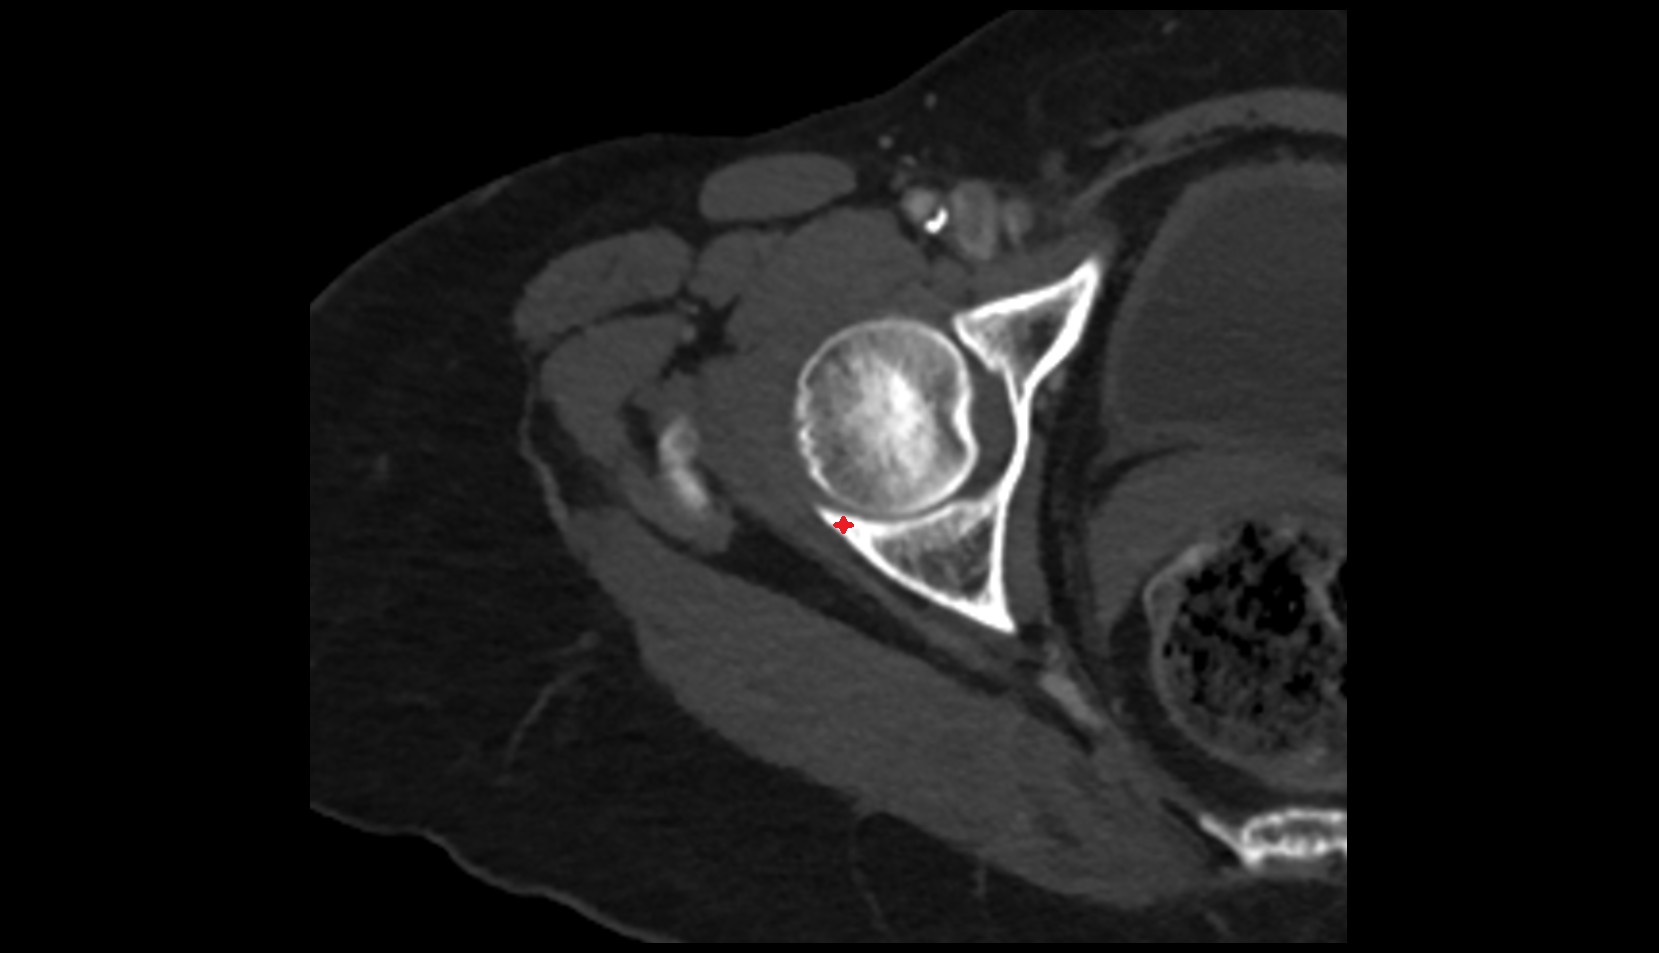

- Head of femur

- Neck of femur

- Femoral artery

- Internal iliac artery